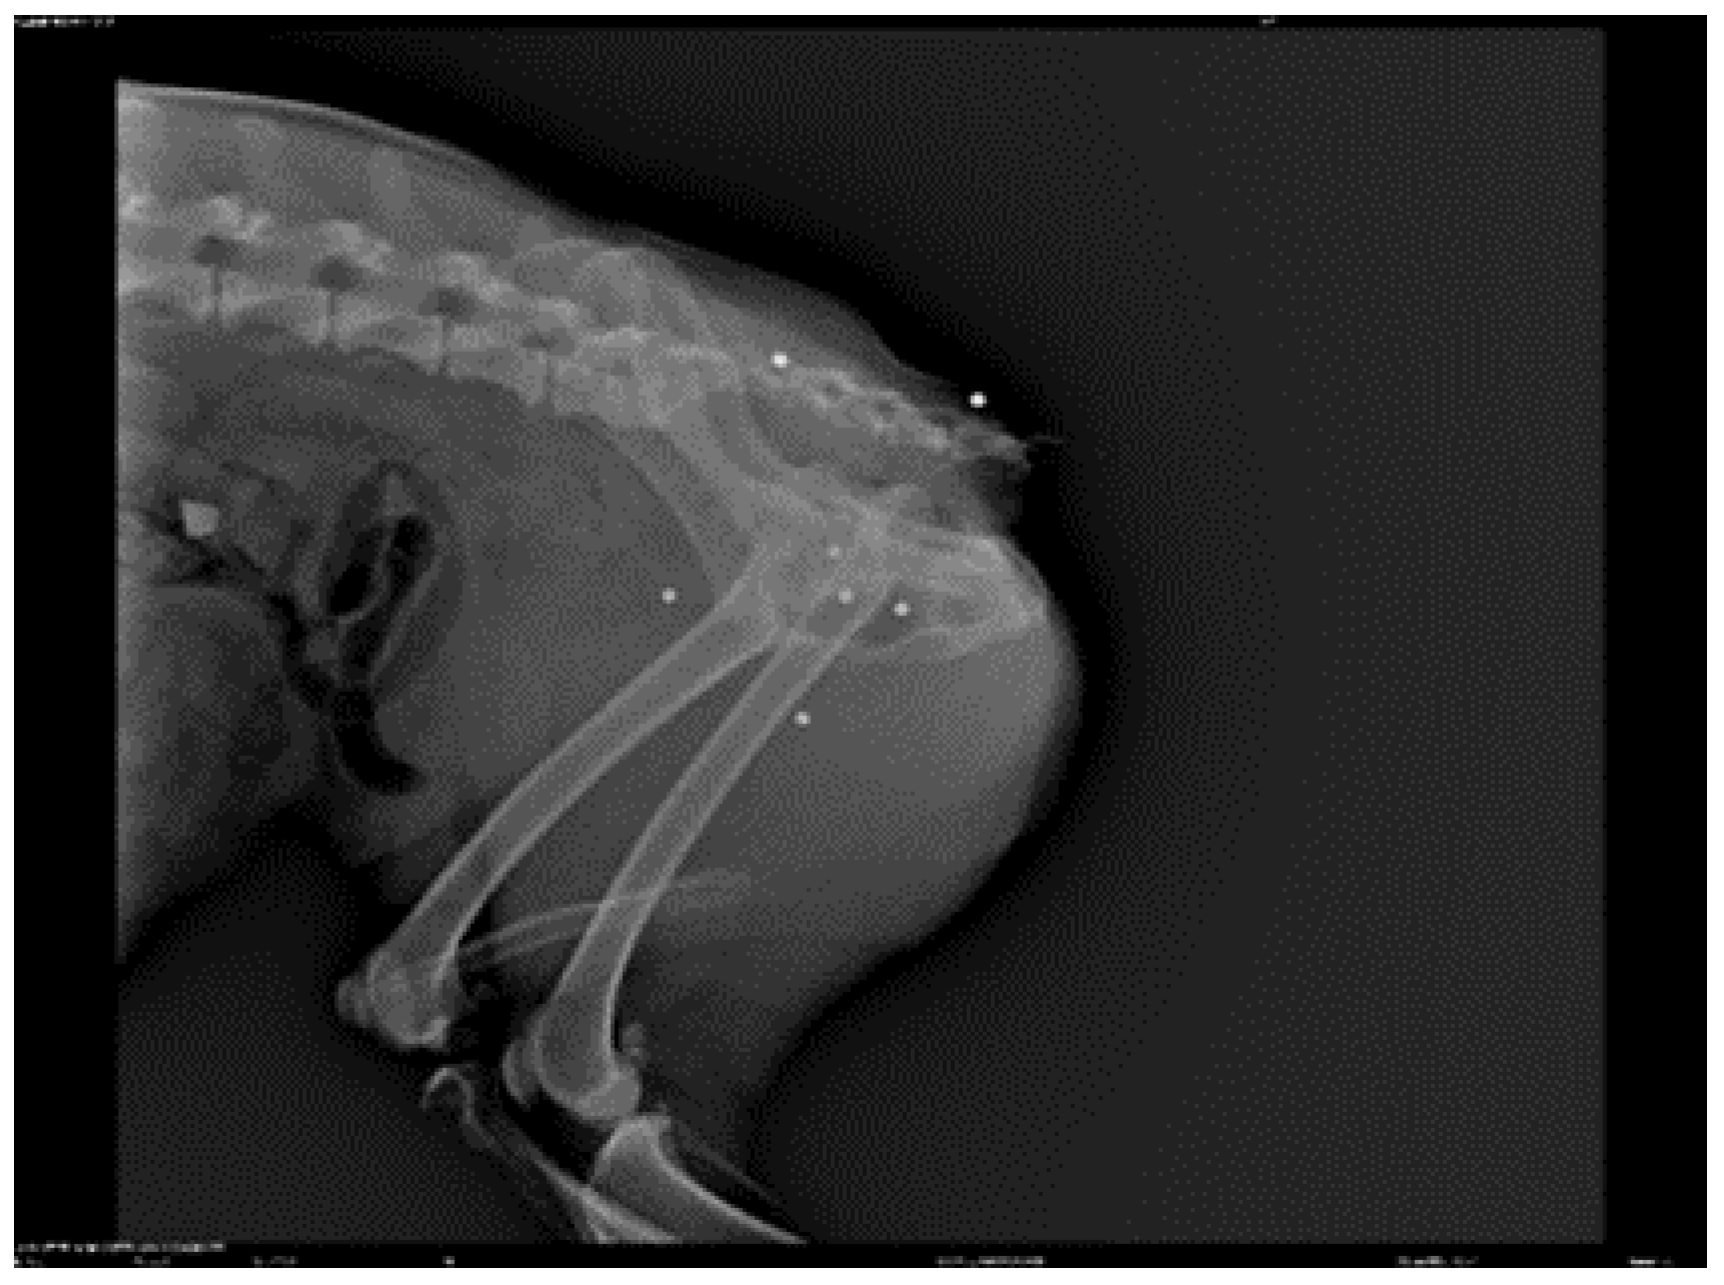

![]() |